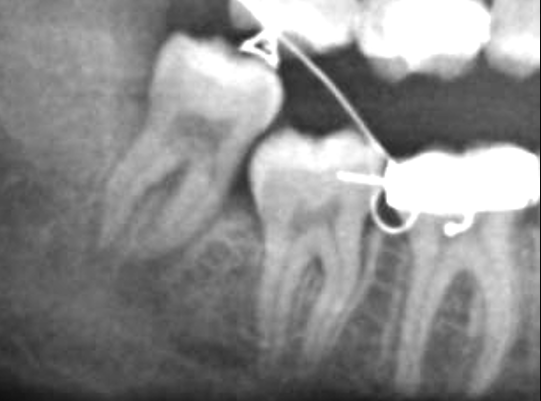

In dettaglio, si tratta di una tecnica combinata tramite la quale sul dente viene affogato un gancetto e sollevato lentamente verso l’alto (quasi fosse una canna da pesca) con una tecnica ortodontica, allontanando il dente dal canale mandibolare. Solo allora il chirurgo potrà intervenire estraendo in piena sicurezza quel dente già mobile e lontano dal nervo mandibolare.